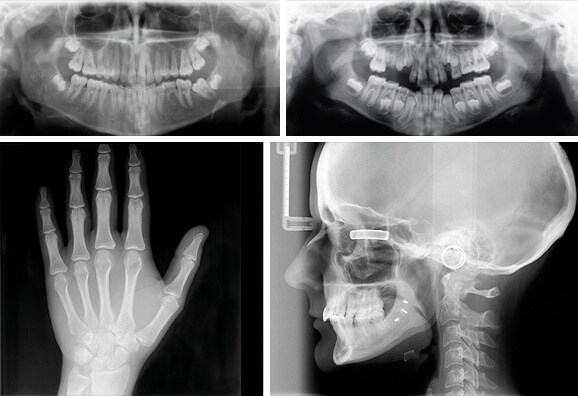

La fonction céphalométrique de CRANEX® D peut être configurée à gauche ou à droite afin de garantir une installation flexible. La visualisation des tissus mous est réglée automatiquement pour une qualité optimale du diagnostic. La fonction AES brevetée permet, elle, de sélectionner les valeurs d'exposition en fonction de la taille du patient.

• combinaison OPG et/ou CEPH